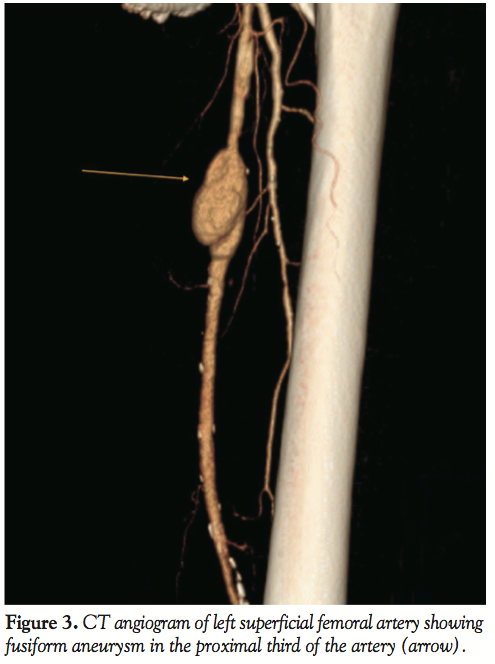

The patient was discharged home the following day without complications. A week later, the patient presented to the hospital with acute onset and worsening pain in his left thigh over the last 3 days and it was associated with ecchymosis and swelling. A CT angiography was performed and showed a fusiform aneurysm 4 cm x 27 mm diameter in the proximal third of the left SFA (Figure 3). Repeat angiogram confirmed the findings (Figure 4). Over a 0.014 ironman wire (Abbott Vascular), a 6.0 mm x 10 cm Viabahn endoprosthesis (W. L. Gore